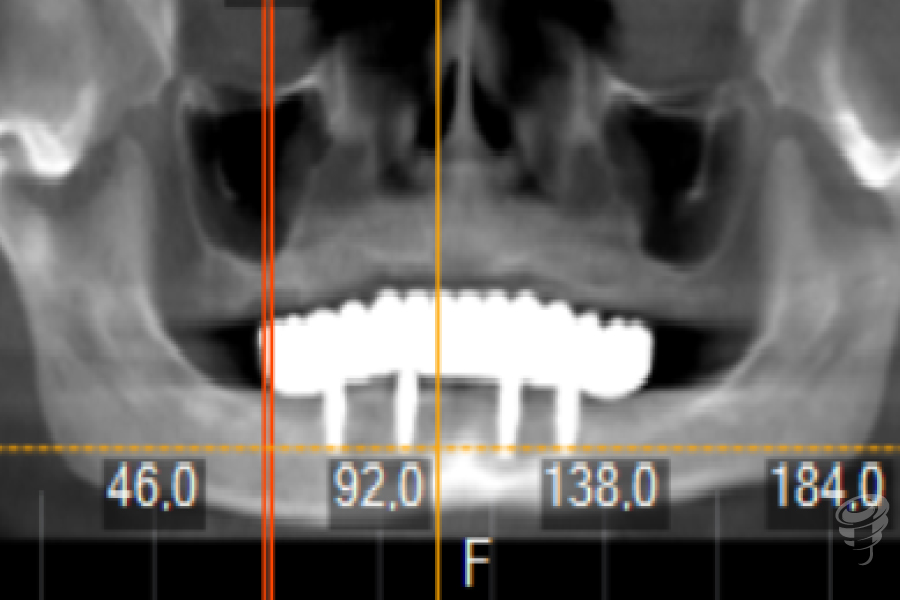

Orto postoperatorio inmediato + Carga inmediata. (Imagen 10 y 11)

Imagen 12

Imagen 13

Orto a los 3 años de evolución + Prótesis definitiva. (Imagen 12 y 13)